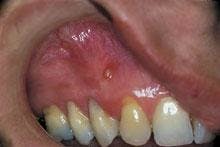

Intraoral examination revealed an elevated yellowish papule near the mucogingival junction and apical to tooth #6 (see photo). The lesion measured three millimeters in diameter and was fluctuant when palpated. A smooth surface without ulceration or hemorrhage was noted. A periodontal probe was used to identify one small opening on the surface of the lesion. Teeth #5 and #6 were pulp tested for vitality; tooth #5 tested vital and tooth #6 tested non-vital. Further examination of the oral cavity revealed no other lesions present. A periapical radiograph of the area was exposed. The radiograph demonstrated a well-defined radiolucency at the apex of tooth #6.

The clinical appearance of the parulis is fairly characteristic. The lesion appears as a yellowish gingival swelling surrounded by erythema. The parulis is fluctuant when palpated and usually measures less than five millimeters in diameter. When examined with a periodontal probe, a small opening into the adjoining fistulous tract can be identified. A purulent exudate can be expressed from this small opening.